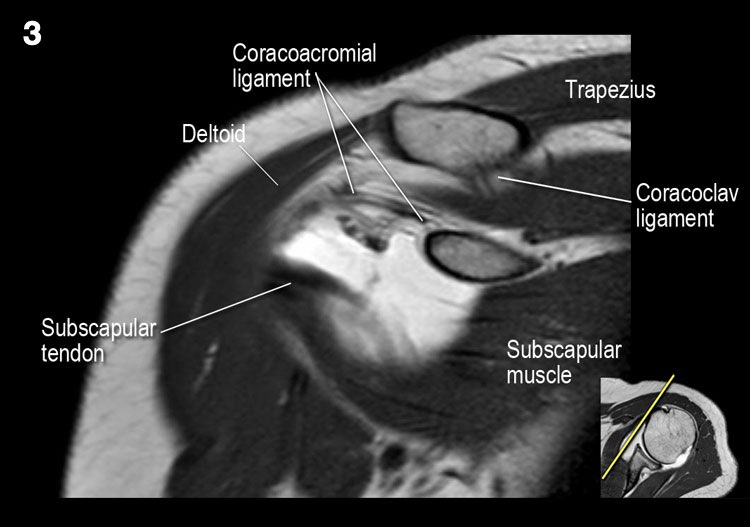

Giải phẫu mặt cắt vành và danh sách kiểm tra

- Lưu ý dây chằng quạ-đòn và đầu ngắn cơ nhị đầu.

- Lưu ý dây chằng quạ-mỏm cùng vai.

- Lưu ý thần kinh và mạch máu trên vai.

- Tìm kiếm hội chứng chèn ép cơ trên gai do gai xương khớp cùng-đòn hoặc dây chằng quạ-mỏm cùng vai dày lên.